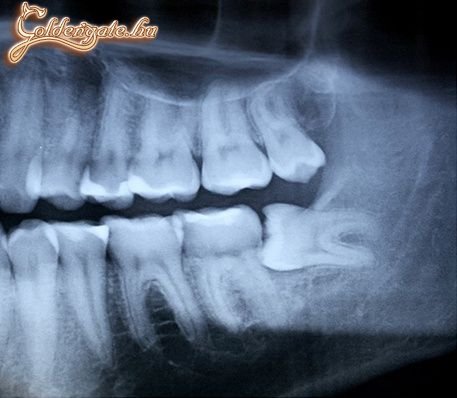

na fasza... nekem is most nől a két alsó bölcsességfogam és baromira fáááááááááj

Ehh, komolyan mondom megijedtem, azt hittem az én álkapcsomról készült képet rakták fel. :D De úgy látom a kommentelők közt is ezt hitték páran. :))))

Nem kamu, nekem is ilyen, én is néztem amikor megláttam a röntgenemet. Ez egy bölcsességfog, ráadásul rejtett.

dögöljön meg, aki kitalálta a bölcsességfogat! múlt héten húzták az enyémet hasonló probléma miatt! szerencsére nekem egyben jött ki!

Nem kunszt: páromnak kettő volt ilyen, mindkettőt szájsebész távolította el.

Éljenek a bölcsességfogak. Nekem is ferdén nőtt az édes, csak nem ennyire.

wazze,lehet,hogy ez az én protkóm? ugyan így nőtt nekem is. ki is kapták a helyéről.